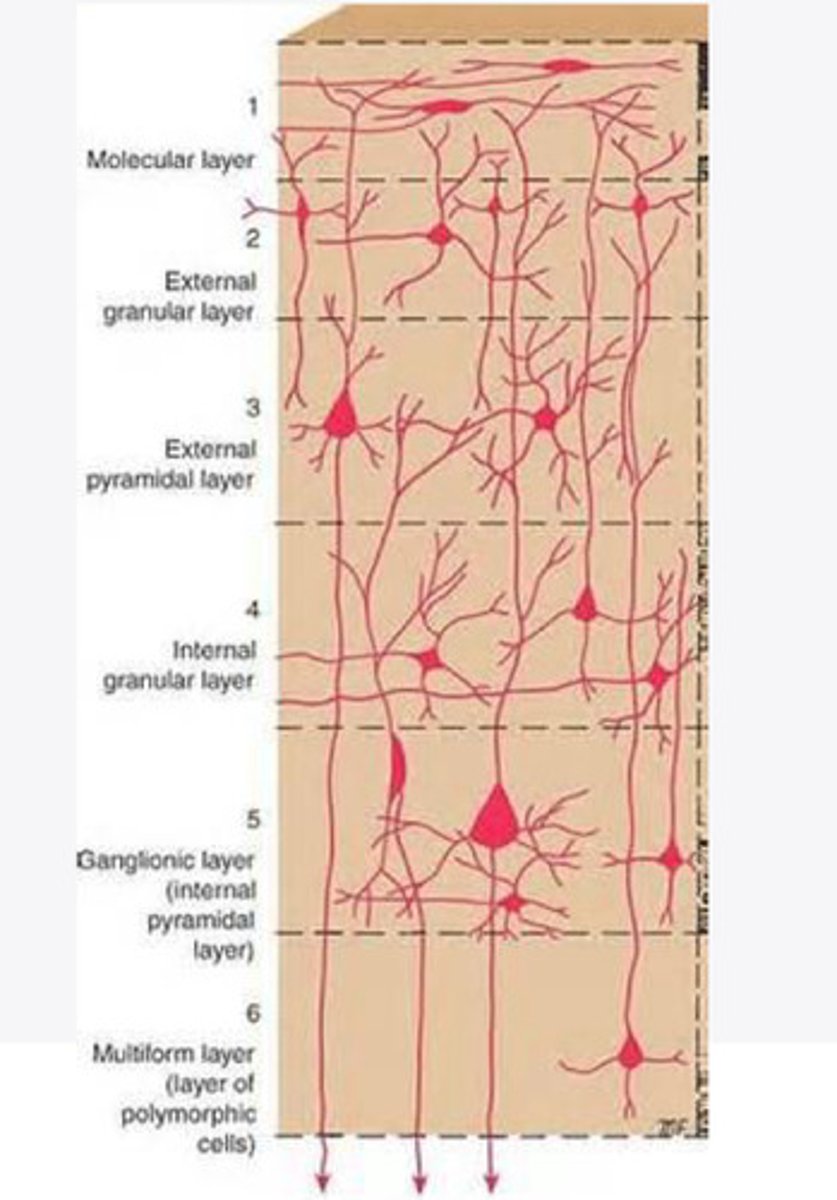

divided into 6 distinct layers, due to varying densities of cell body types within each layer

The cortex of the brain is divided into how many layers? Why is it divided into layers?

Layers of the cortex of the brain pic

2 and 4

What are the layers of the cortex that are associated with input?

3 and 5

What are the layers of the cortex that are associated with output?

molecular layer

What is the name of Layer 1 of the cortex of the brain?

very few cells

Does Layer 1 of the cortex have a lot or few cells?

receives dendrites from internal layers so it may actually function as a coordinating center where layers can communicate action

What does Layer 1 of the cortex do?

1

Every layer sends densities to Layer ____?

1

What layer serves as the "water cooler" of the brain?

external granular layer

What is the name for layer 2 of the cortex of the brain?

receives input from other cortical regions

What is the function of Layer 2 of the Cortex of the brain?

Stellate

What type of cells (stellate/pyramidal) would be most concentrated in Layer 2?

external pyramidal layer

What is the name for layer 3 of the cortex of the brain?

sends output to the other cortical layers

What is the function of Layer 3 of the cortex of the brain?

pyramidal

What type of cells (stellate/pyramidal) would be most concentrated in Layer 3 of the brain?

Layers 2 and 3

What layers are associated with association and commissural fibers?

Layer 3 - axons of cell bodies

Layer 2 - synapse into target areas in Layer 2

What part of the axons is in Layer 2/ in layer 3?

Layer 3 - external pyramidal layer

All axonal cel bodies for association and commissural fibers lie within what layer of the Cortex of the brain?

internal granular

** or called the striate cortex because it is so thick that you can see a line through this layer even in unstrained brain slides

What is the name for the 4th layer of the cortex of the brain?

receives input from the thalamus, geniculocortical layer, and other brainstem areas

What is the function for the 4th layer of the Cortex of the brain?

very thick within the vision, auditory, and somatosensory areas

Is Layer 4 thick or thin within SENSORY areas of the cortex?

Internal pyramidal

What is the name for Layer 5 of the cortex of the brain?

sends axons to the brainstem (corticobulbar) and spinal cord (corticospinal)

What is the function of Layer 5 of the cortex of the brain?

in motor areas of the cortex?

Where is layer 5 very thick in the brain?

the frontal lobe -- very motor heavy

What lobe of the brain will have a thick layer 5 of the cortex of the brain?

the multiform layer

What is the name of layer 6 of the cortex of the brain?

-sends axons back to the thalamus through corticogeniculate fibers

-modulates what information the thalamus sends to the cortex to control the strength of the signal received and modulate what you pay attention to

What is the function of layer 6 of the cortex of the brain?

no

Is layer 6 a motor layer?